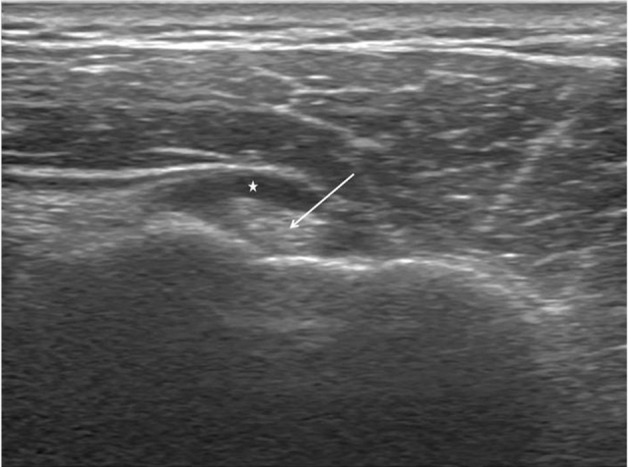

In the transverse sonographic view, tenosynovitis of the long head of the biceps tendon appears like a fried egg due to a halo effect of hypoechoic effusion near the dense shadow of the long head of the biceps tendon (Fig. 4) [11]. A partial-thickness tear could appear as a crevice (Fig. 5), while a full-thickness tear may not be visible because of an involution. Rupture is often accompanied by medial dislocation of the long head of the biceps tendon [12].

Fig. 4.

Sonographic finding of long head of the biceps tendinitis. The arrow indicates the long head of the biceps tendon. The asterisk indicates effusion surrounding the long head of the biceps tendon. The shape is similar to that of a fried egg.